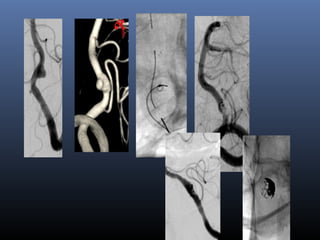

Very small aneurysms …

Dissecting

blister

aneurysm –

poor grade

EVD

2-overlapping Enterprise stents

Blister/

aneurysms